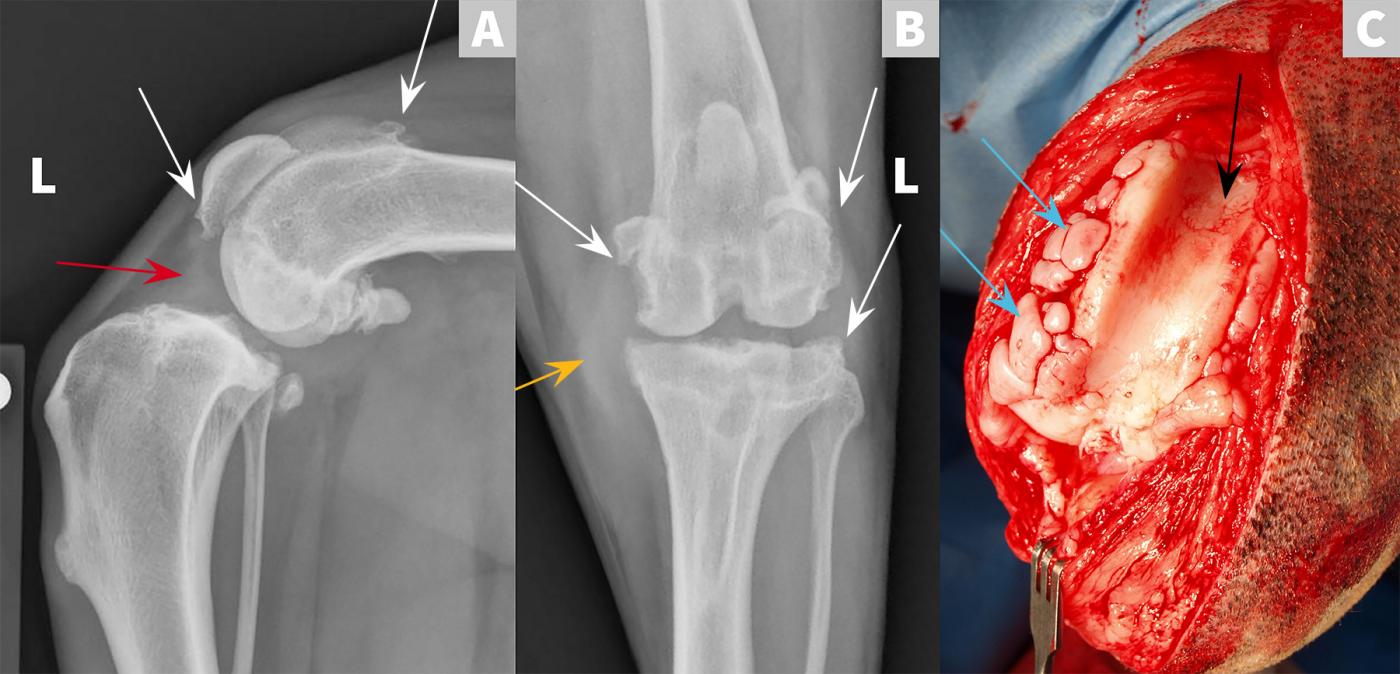

From www.cliniciansbrief.com